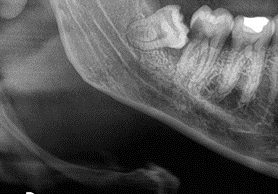

• Risk of decay or damage to adjacent teeth Example: An impacted lower right wisdom tooth causing decay on the back surface of the adjacent molar. Ideally, the wisdom tooth should be removed before this occurs.